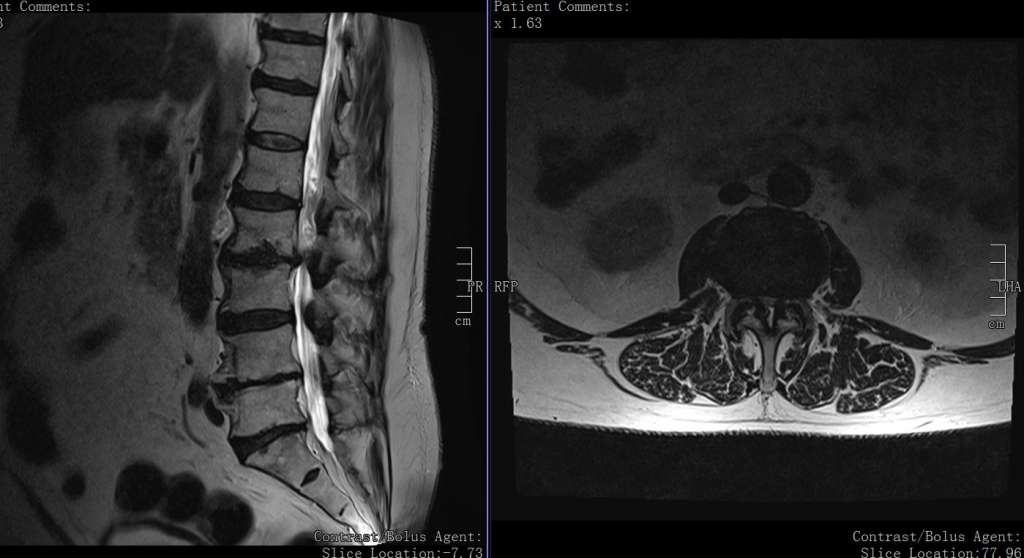

Treten nach mehreren Jahren plötzlich Beschwerden auf, sollten Patienten in jedem Fall einen Facharzt aufsuchen. Manchmal ergeben sich aus der Versteifung der Wirbelsäule Ausgleichsbelastungen. Dies bedeutet, dass der Patient die eingeschränkte Flexibilität der Wirbelsäule durch Schonung oder eine veränderte Haltung ausgleichen möchte.. Postoperative Betreuung nach Wirbelsäulen-OP: Tipps & Ratschläge . Du hast eine Operation an deiner Wirbelsäule hinter dir und überlegst, was jetzt zu tun ist? Es ist völlig normal, dass du nach der OP Schmerzen und Beschwerden hast. Es kann Wochen oder sogar Monate dauern, bis du dich wieder vollständig erholt hast.